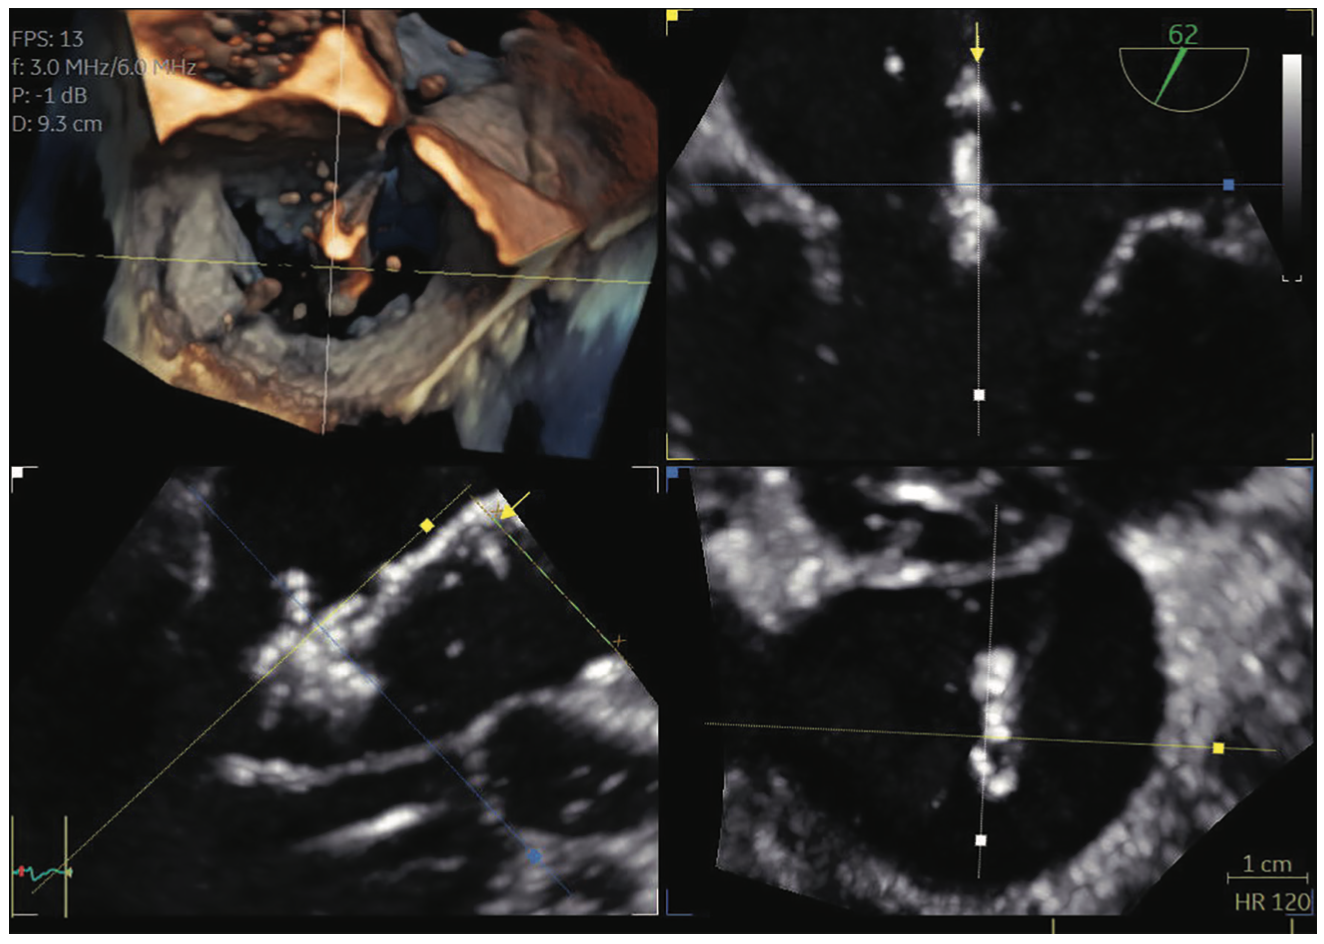

In real life, catheters and cardiac structures don’t exist in perfect 2D planes, but in 3D space, so we frequently rely on 3D technology to guide structural heart procedures. We recently performed a transcatheter mitral valve intervention with MitraClip, and we were not able to guide device placement with routine 2D imaging because we couldn’t visualize the MitraClip delivery system in conventional 2D imaging planes. However, we were able to utilize live multiplanar 3D imaging with FlexiSlice (GE HealthCare), which allowed us to manipulate the imaging planes such that the guide catheter, delivery system and MitraClip could be visualized in a single imaging plane. The technology allowed us to visualize and implant the device with ease, resulting in a good outcome for the patient.

We are also starting to use fusion technology. There are several different types of fusion imaging technology currently available on the market; one recently released fusion technology is CT-Echo Fusion (GE HealthCare) that fuses previously acquired CT data to the live 3D echo image. Echocardiography can suffer due to dropout from calcification or devices. This fusion technology allows us to integrate CT imaging that we already utilize for pre-procedural planning of structural heart procedures and integrate that with the echocardiographic images obtained on the day of the procedure. These fusion technologies are currently evolving and may prove to be very useful in complex structural heart procedures where echocardiography alone may not be sufficient.

Another new technology called FlexiLight imaging (GE HealthCare) is a new 3D rendering technique that provides photorealistic, light-source-based illumination of heart structures that help the imager with depth perception when visualizing cardiac structures. This imaging technique can provide realistic detail of the contours of cardiac structures that we have not been able to appreciate previously. FlexiLight can also potentially better illustrate the interaction of devices with valve leaflets, or when complications such as leaflet perforation may have occurred.

I also want to note the recent development of the new mini 3D TEE probe (GE HealthCare), which will be very useful in certain patient populations such as pediatric patients, smaller adult patients, or those in whom general anesthesia may not be able to be utilized. This type of technology has not been available in the past. We often want to perform structural heart procedures when patients are not fully intubated or anesthetized, so a miniature 3D TEE probe is potentially a very useful technology that may allow us to utilize TEE when the patient is only under moderate sedation. In cases of smaller-statured patients, we have had difficulty in certain instances in placing the larger, full-sized TEE probe. We have utilized pediatric probes in the past, but they previously were limited to 2D imaging. Having a new pediatric-sized probe with 3D multiplanar imaging is definitely a game changer.